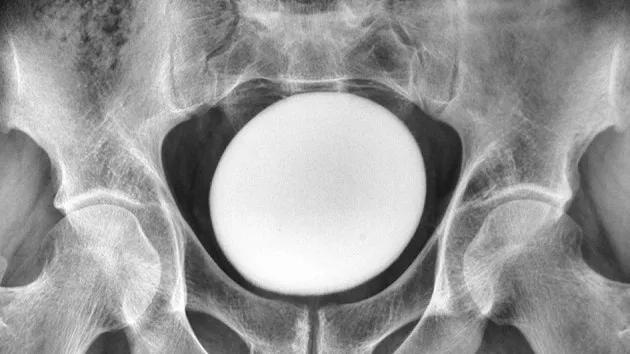

의사들은 환자의 복부를 진찰하던 중 치골 위에서 크고 매끄러우며 단단한 덩어리가 만져져 초음파 검사를 실시했다. 그 결과 환자의 방광 안에 지름 11㎝의 커다란 결석이 있음을 확인했다.

해당 남성은 방광 절개술을 받고 결석을 제거했다. 제거된 결석은 길이 13㎝, 너비 10㎝, 높이 8㎝로 무게만 약 826g에 달한 것으로 알려졌다.